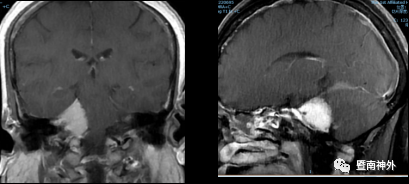

术前影像学检查:

右侧桥小脑角区见一团块状异常信号影,大小约3.6×2.5cm,宽基底,病灶呈等T1WI稍长T2WI信号,DWI呈高信号影,邻近桥脑右侧份受压推移,增强扫描病灶呈明显较均匀强化,可见脑膜尾征。